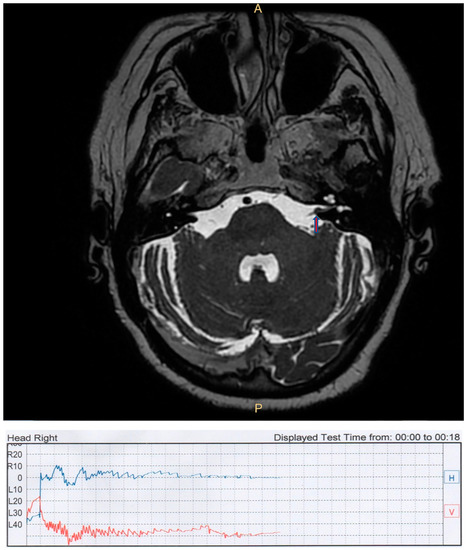

| CC | female | 69 | protruding CPA | right | geotropic direction-changing PPN | first sign | not responsive |